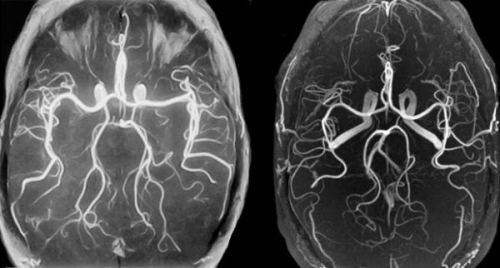

У магнітно-резонансної ангіографії довга історія. Відкриття в 1895 році Рентгеном нового виду випромінювання